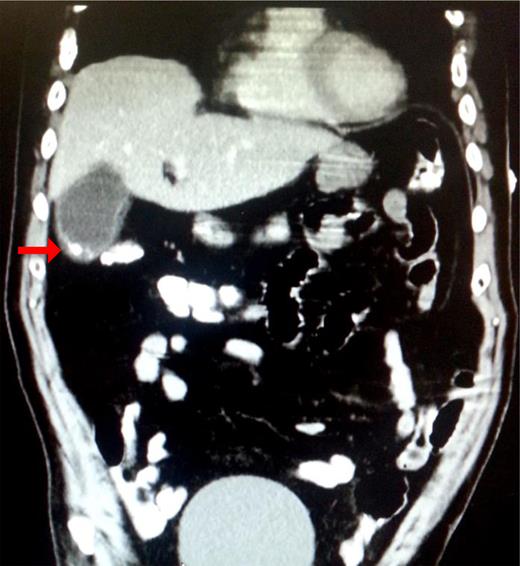

Electrocardiogram showed sinus tachycardia with frequent premature ventricular complexes. Abdominal and pelvic computed tomographic (CT) scan revealed a distended gallbladder with calculi in the fundus, gallbladder wall thickening and pericholecystic fluid [Fig. 1]. Diffuse osteopenia and multiple punched-out lytic lesions in the axial skeleton consistent with multiple myeloma were reported on the CT scan.

Mural calcification and/or stone in the fundus of the gallbladder (red arrow).